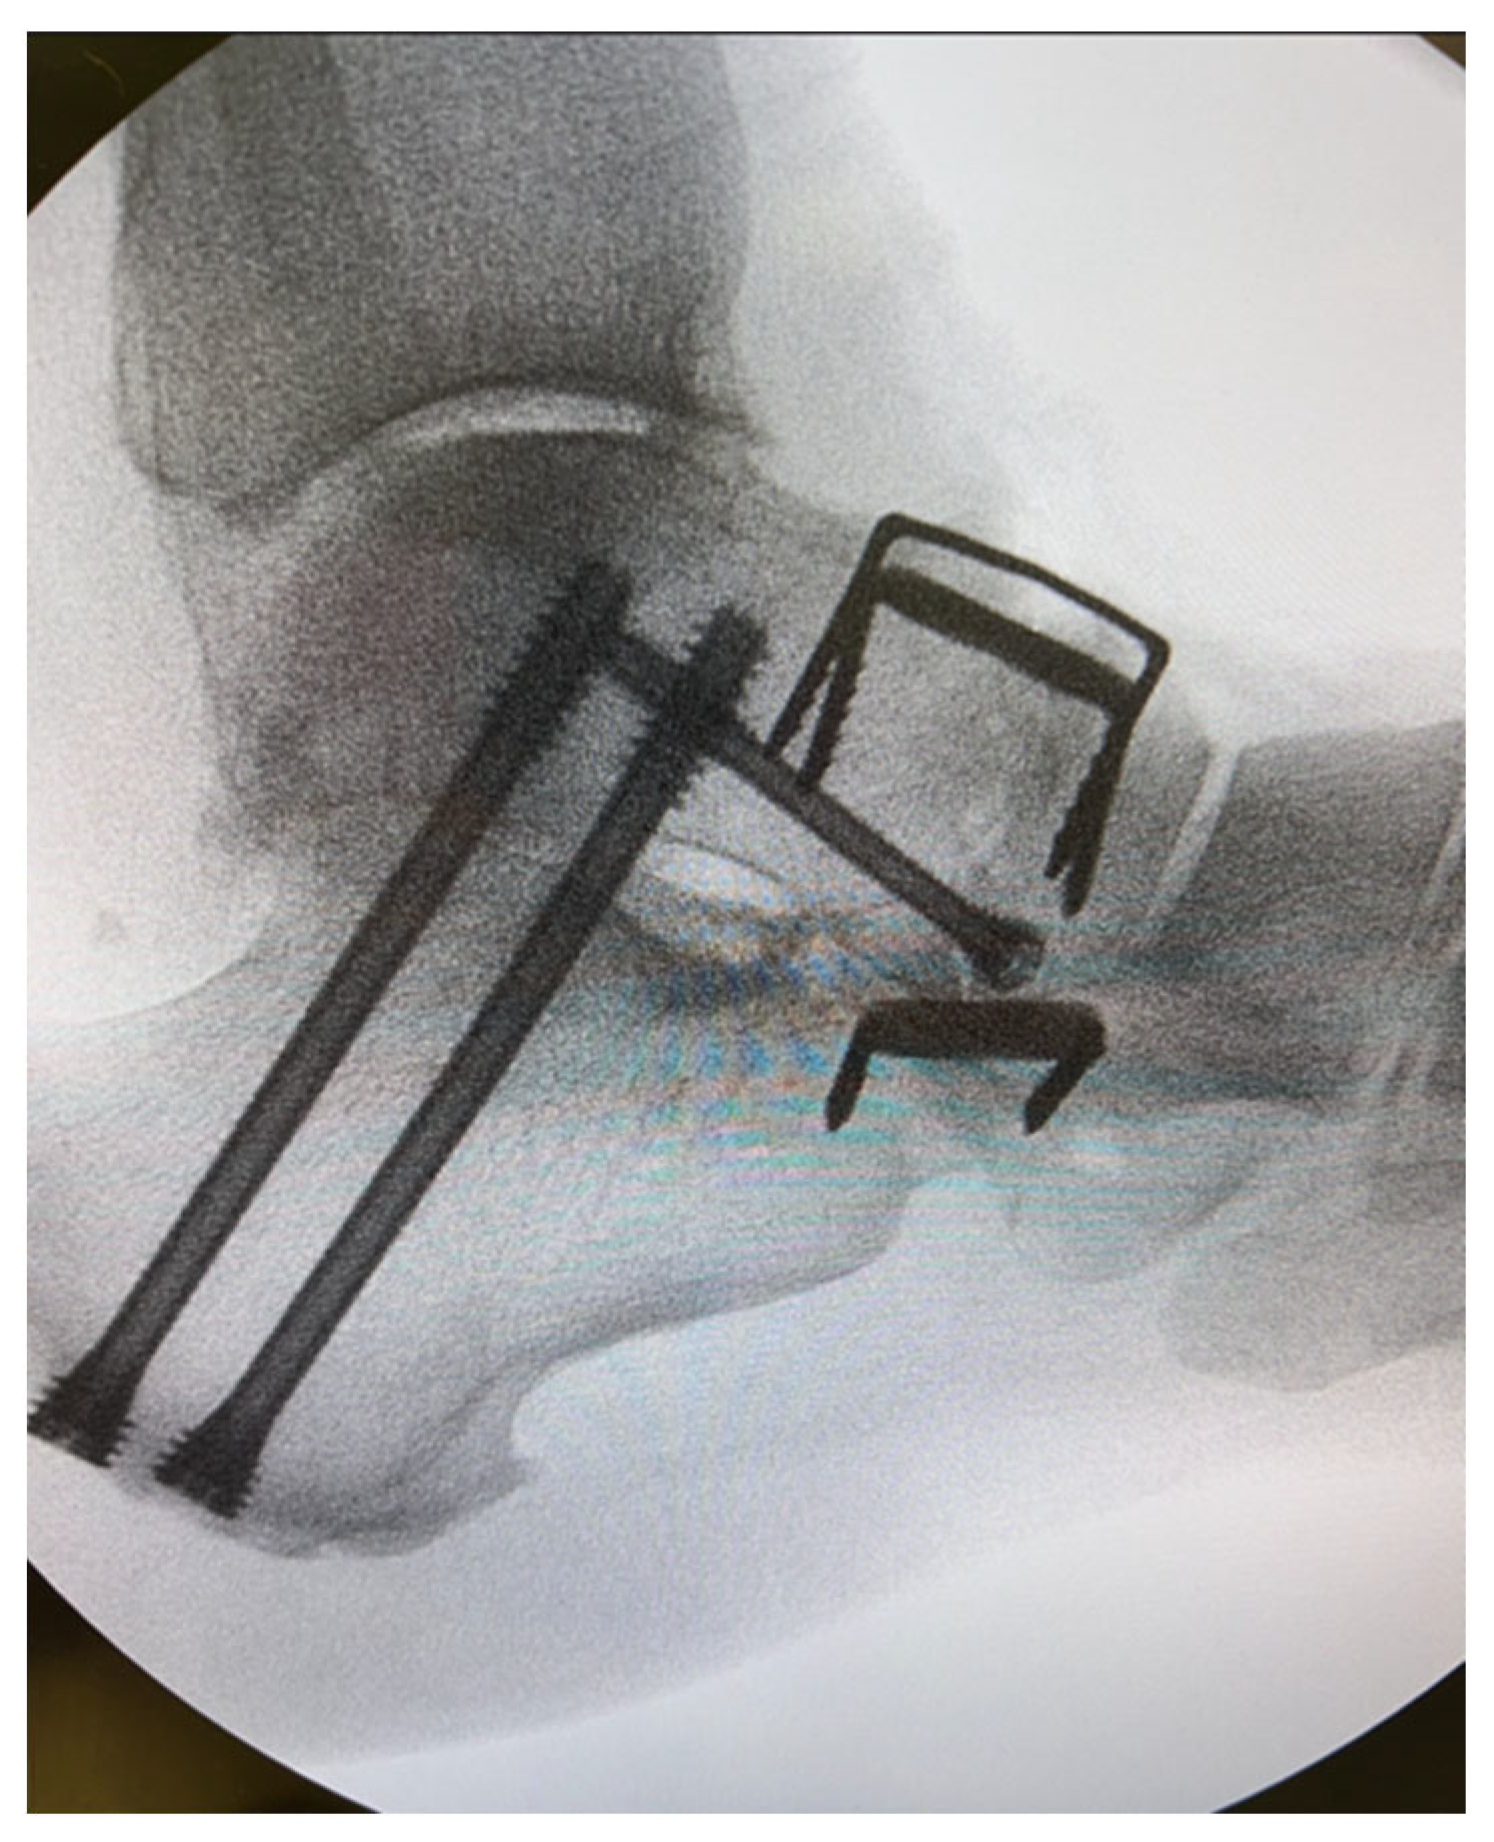

In terms of the legs of the staples, there are no clear recommendations in the literature at the moment. From a biomechanical perspective, where possible, four-leg staples should be utilised to allow for the even distribution of compression forces through the tips. For instance, this could be the case for the first tarsometatarsal joint [2] (Figure 3). Of note, dual-staple constructs applied in an orthogonal fashion provide greater than doubled compression in comparison to constructs with a single staple. Moreover, double-staple constructs appear to be 2 times stiffer than plate constructs. This finding may have potential implications in clinical practice as double-staple constructs should be used where feasible [5].

Figure 3. Intra-operative radiographs depicting fusion of tarsometatarsal joints with a combination of two- and four-leg staples.